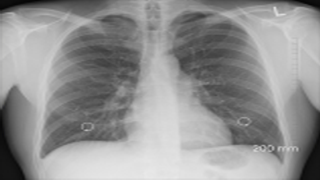

폐렴은 모든 사람들에게 영향을 미칠 수 있는 심각한 폐 감염으로, 한쪽 또는 양쪽 폐에 염증이 생기는 질병입니다. 한쪽 혹은 양쪽 폐에 고름이 차서 기침, 발열, 오한, 호흡 곤란과 같은 증상을 유발할 수 있습니다. 이 질환은 특히 고령의 성인, 아기, 면역력이 약화된 사람들에게 생명에 지장을 줄 수 있습니다. 이 글에서는 폐렴에 대해 자세히 살펴보고 이 심각한 질병의 위협을 줄이는 효과적인 방법에 대해 알아보겠습니다.